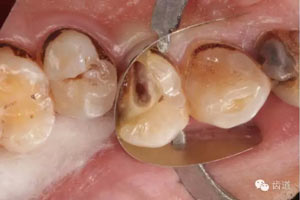

檢查:14遠(yuǎn)中鄰頜面探及齲壞至牙本質(zhì)深 層,穿髓。探-,冷-,叩-。松動(dòng)-。牙齦無(wú)紅腫,未探及牙周袋。

數(shù)碼攝影x片顯示:14遠(yuǎn)中鄰頜面暗影,穿髓。根尖暗影。無(wú)牙周膜增寬。

處理:去齲,擴(kuò)大穿髓孔,揭髓室頂,根管探查,探及頰腭兩根管口,去除牙本質(zhì)肩領(lǐng),根管疏通:k file10#至15#。確定wl。鎳鈦器械M Two根管預(yù)備至2506。根管預(yù)備中大量使用1%次氯酸鈉和17%edta溶液。預(yù)備結(jié)束后生理鹽水結(jié)合超聲蕩洗,干燥根管,根管內(nèi)放置氫氧化鈣糊劑,Zoe暫封。